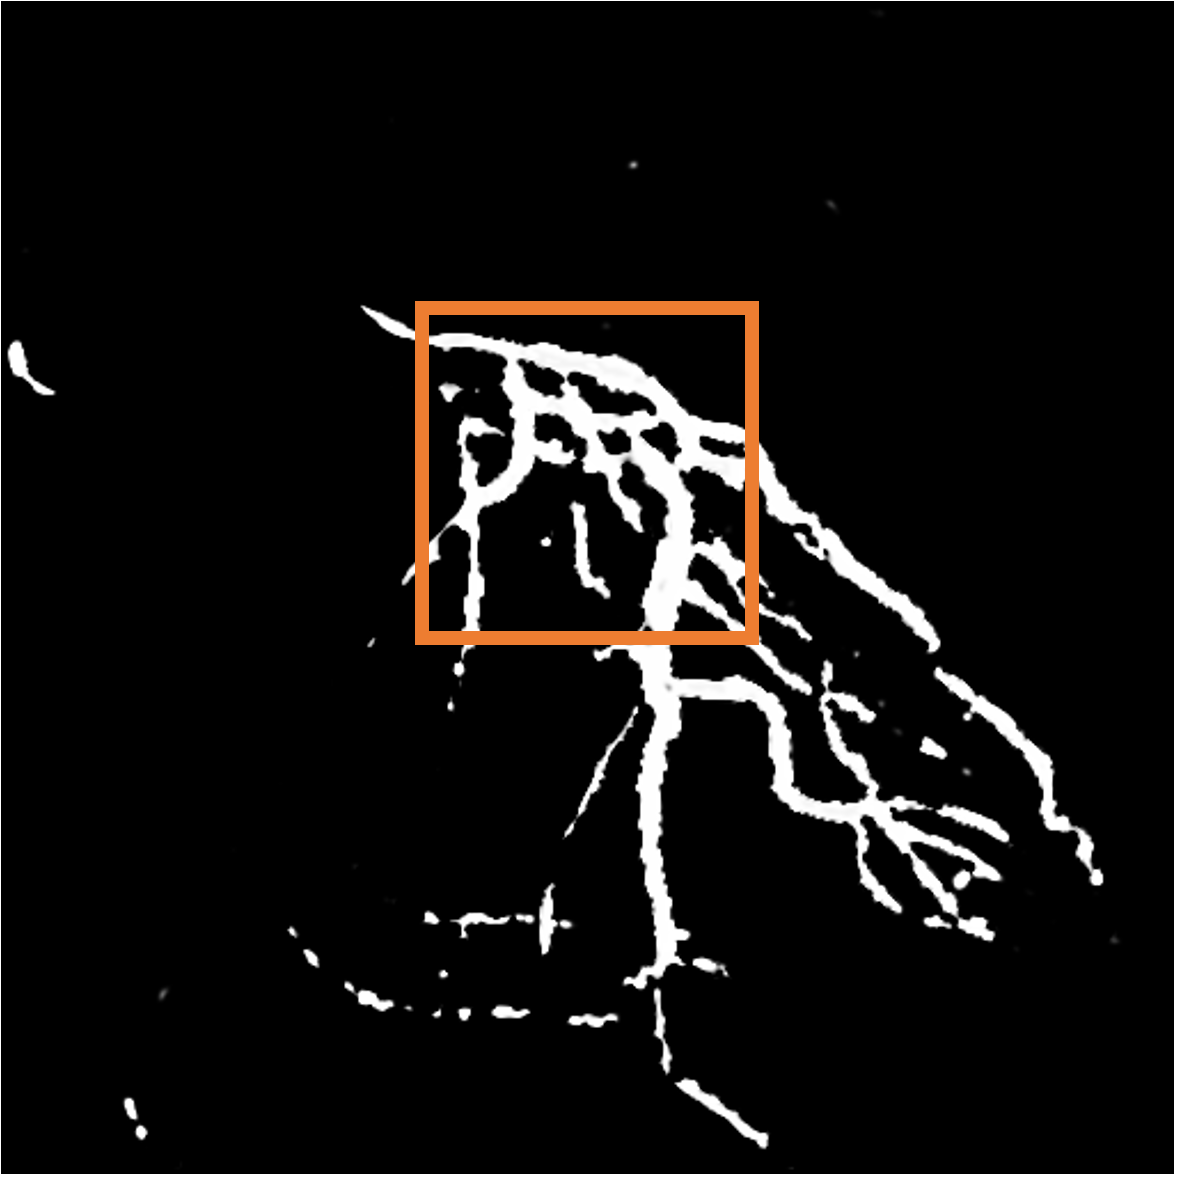

Layer separation bootstrapping.

To validate the effectiveness of the layer separation bootstrapping, we train foreground and background canonical images using the same representation. The results are shown in Table 2, where optimizing both foreground and background canonical images simultaneously leads to a decrease in the Dice score by 0.0877. The comparison is shown in Figure 9 (a), where the orange area indicates the difference between without and with Layer separation bootstrapping. The bottom-right corner shows a zoom-in patch, highlighting the significant effect of the bootstrapping step.